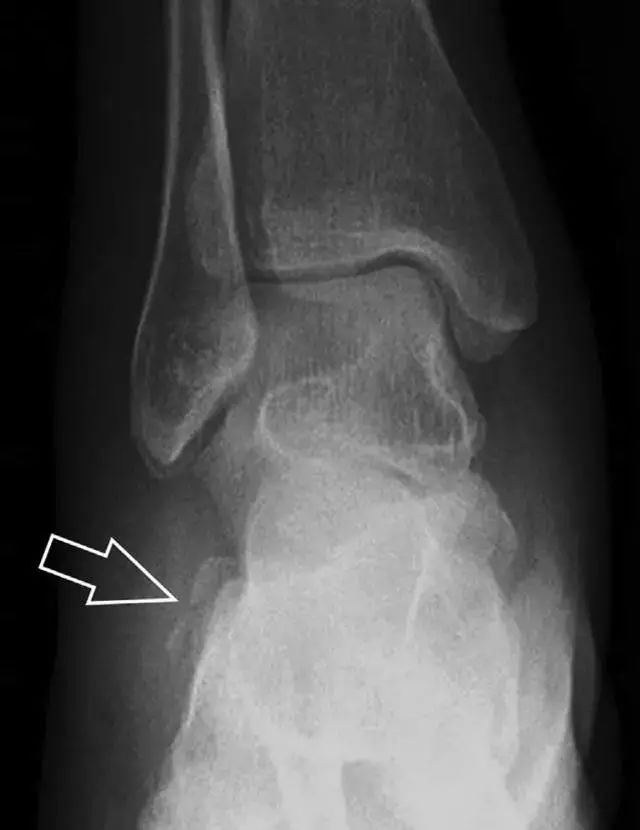

16

胫骨后踝骨折

涉及到三角韧带和外侧副韧带(LCL)的复杂性骨折常常不难发现,尤其是存在表面软组织肿胀时。然而,后胫腓韧带牵拉引起的胫骨后踝骨折则很难发现。这些骨折大小不一(图 2),却很重要,因为他们常与胫骨远端螺旋骨折有关,或者是三踝骨折的一部分。

图 2 胫骨后踝骨折。A 侧位片示来源于胫骨后踝的一个小骨折碎片(箭头),因踝部扭伤导致;B 另一位跖屈损伤的患者,侧位片示一个大骨折块(箭头)。

17

胫骨结节骨折

Tillaux 骨折,是足外旋外展时,胫腓前韧带牵拉引起的一种胫骨结节撕脱性骨折。斜位片上可见典型表现(图 3)。

图 3 摔倒后胫骨结节骨折。A 正位片示一细小斜型骨折线(箭头);B 侧位片示正常;C 冠状位 CT 三维成像更清晰地显示了骨折线和骨折块大小(空箭头);D 矢状位 CT 多维重建图像示骨折位置(箭头)。